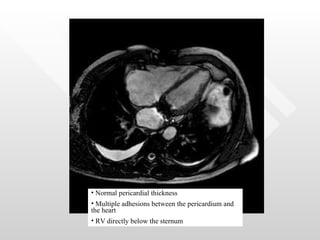

Normal pericardial thickness Multiple adhesions between the pericardium and the heart RV directly below the sternum

Normal pericardial thicknessMultiple adhesions between the pericardium and the heart RV directly below the sternum